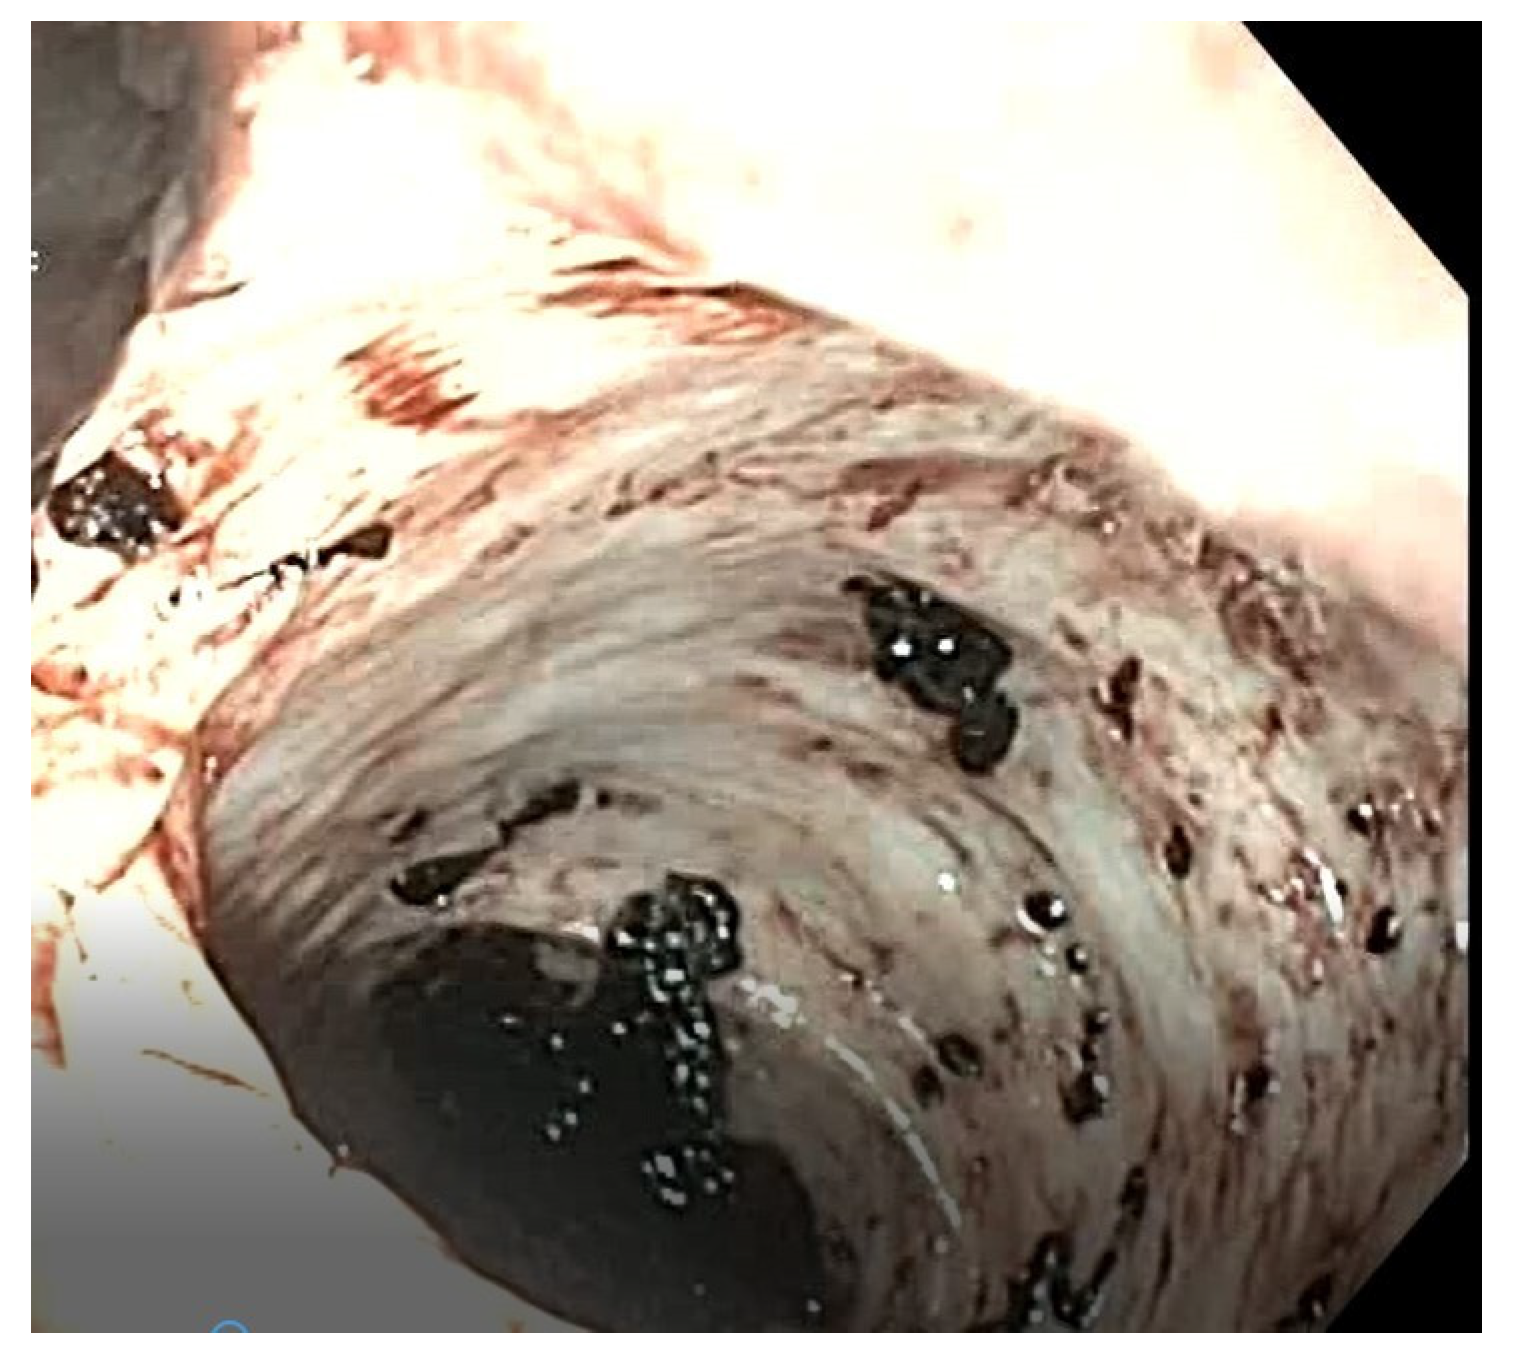

Figure 5.

Case 3—Endoscopic image showing fecal residues with melena appearence.